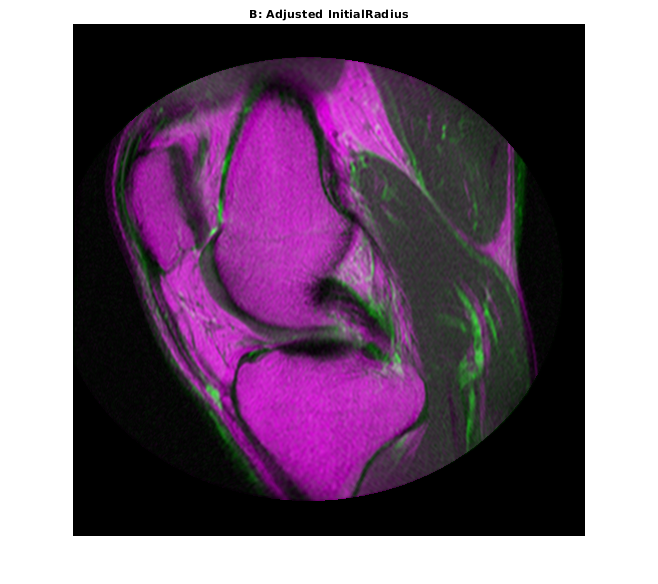

Свойство InitialRadius оптимизатора управляет начальным размером шага, используемым в пространстве параметров, чтобы совершенствовать геометрическое преобразование. Когда многомодальные регистрационные проблемы не сходятся с параметрами по умолчанию, InitialRadius является хорошим первым параметром, который настроит. Запустите путем сокращения значения по умолчанию InitialRadius масштабным коэффициентом 3,5.

optimizer.InitialRadius = optimizer.InitialRadius/3.5; movingRegisteredAdjustedInitialRadius = imregister(moving,fixed,'affine',optimizer,metric); imshowpair(movingRegisteredAdjustedInitialRadius,fixed) title('B: Adjusted InitialRadius')

Корректировка InitialRadius оказала позитивное влияние. Существует значимое улучшение выравнивания изображений на верхних и правых краях.